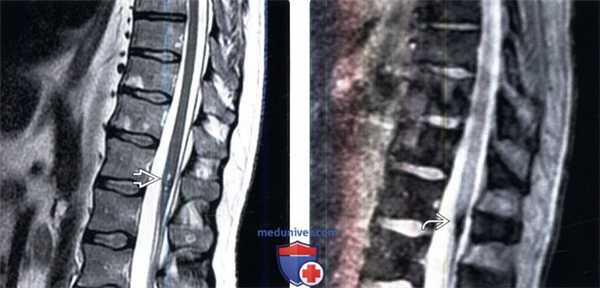

(Слева) На сагиттальном Т1 -ВИ у пациента с интрадуральной фистулой 4 типа визуализируются многочисленные извитые сосудистые полости вдоль дорзальной поверхности спинного мозга.

(Справа) Ангиография в прямой проекции: фистула 4 типа, кровоснабжаемая правой корешковой артерией, контрастированы многочисленные расширенные перимедуллярные вены.

(Слева) На фронтальной КТ-ангиограмме визуализируется крупный клубок сосудов вдоль вентральной поверхности спинного мозга, кровоснабжаемый правой корешковой артерией и характеризующийся расширением вен на поверхности спинного мозга.

(Справа) Ангиография в прямой проекции: сосудистая мальформация, кровоснабжаемая корешковой артерией на поверхности спинного мозга. Шунтирование крови осуществляется на уровне спинного мозга (4 тип), а не на уровне твердой мозговой оболочки (1 тип).